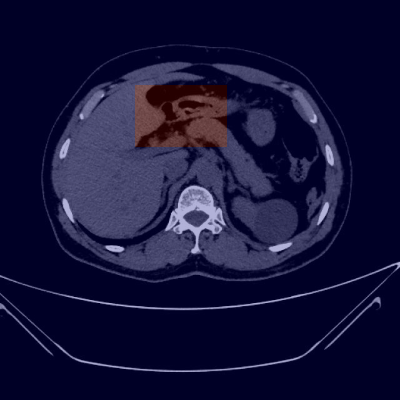

1.4.3. 典型案例分析

上图展示了几个典型病例的检测结果。第一行展示了囊肿的检测结果,模型能够准确识别囊肿的位置并生成精确的分割掩膜;第二行展示了肾脏区域的分割结果,模型能够完整勾勒出肾脏的轮廓;第三行展示了结石的检测结果,虽然结石尺寸较小,但模型仍然能够准确定位;第四行展示了肿瘤的检测结果,模型能够区分肿瘤与周围正常组织。

这些案例表明,我们的方法在实际临床应用中具有很高的实用价值,能够辅助医生快速准确地识别和定位肾衰竭病变,提高诊断效率和准确性。👨⚕️